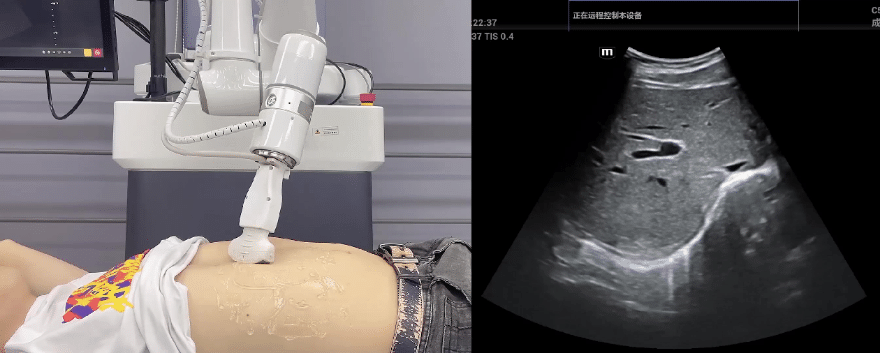

米兰·(milan)中国协作机器人搭载库柏特自主研发的机器人遥操作、多模态数据采集与处理、机器人模仿学习、机器人力位控制等技术升级变革传统超声,可实现远程+自主超声扫查与诊断,从传统远程超声仅能对话会诊变革升级为能对话、能操作,使得基层患者可就近享受异地三甲专家扫诊服务。实现专家端与患者端远程连接,并支持专家端与多路患者端自由切换控制。

米兰·(milan)中国机器人末端搭载超生L13-3N线阵探头,可以对浅表小器官和外周血管进行超声检查;搭建C5-1s凸阵探头,可以对腹部(肝、胆、胰、肾等器官进行超声检查)

EC66协作机器人末端可搭载主流品牌高品质超声仪,让操作指令和影像低延迟、高精准、高保真传输,确保检查可靠、医患放心;智能力控等三重防护系统,确保患者舒适、安全。

米兰·(milan)中国协作机器人与超声深度打通,最大程度保留医生左右手同时操作传统超声的习惯,并改善其舒适性,超声检查实际应用场景展示如下: